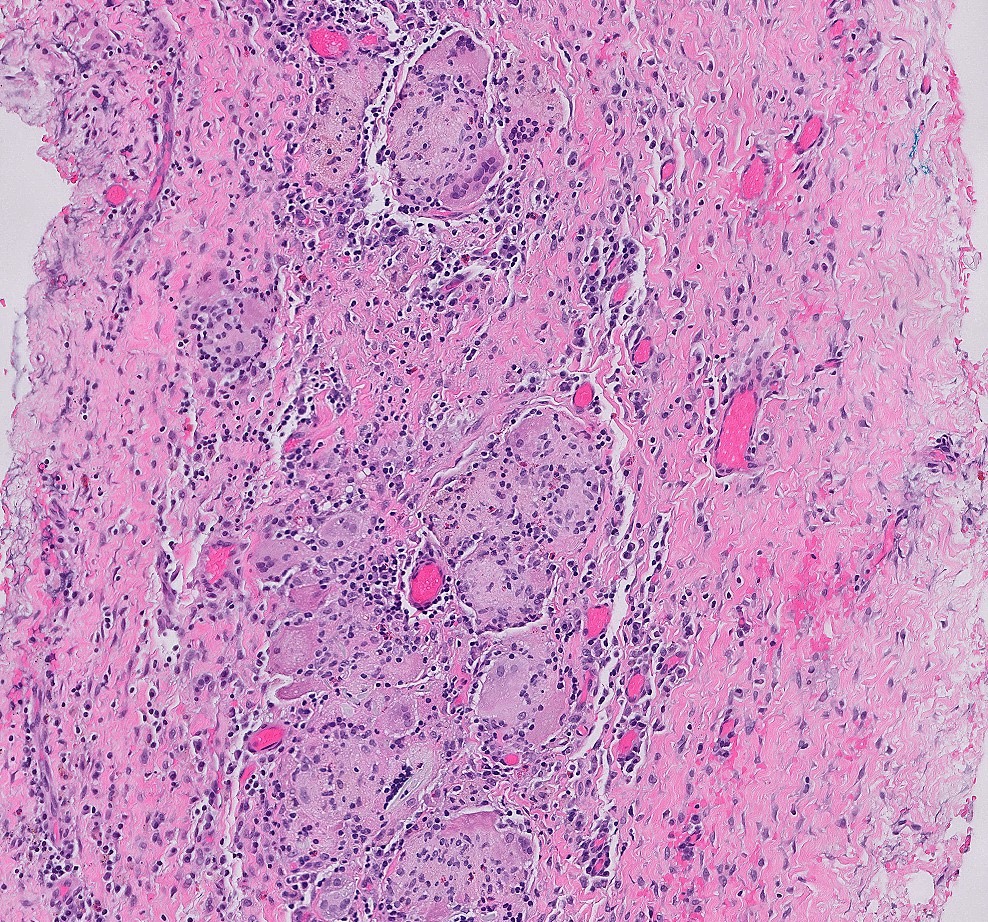

Microscopic (histologic) description

- Mucosa may be normal to markedly abnormal

- Expansion of lamina propria by lymphoplasmacytic infiltrate (more prominent in basal half)

- Lymphoglandular complexes, mucin depletion, focal Paneth cell metaplasia (in chronic cases) may be seen (J Clin Gastroenterol 2004;38:S11)

- Hemosiderin deposition in submucosa may be seen (StatPearls: Diverticulosis [Accessed 21 April 2022])

- Can mimic inflammatory bowel disease

- Hyperplasia of lymphoid aggregates is one of the earliest signs of diverticulitis

- Cryptitis, crypt abscesses, peridiverticular abscess and fistulas may be superimposed on this background in acute diverticulitis

- Tracking abscesses can spread longitudinally or circumferentially and can cause diverticular colitis

- Persistent localized inflammation can lead to phlegmon which is a thickened, firm segment of bowel wall that can lead to strictures and acute or subacute large bowel obstruction (Best Pract Res Clin Gastroenterol 2002;16:543)

Microscopic (histologic) images

Contributed by Bindu Challa, M.D. and Martha M. Yearsley, M.D.